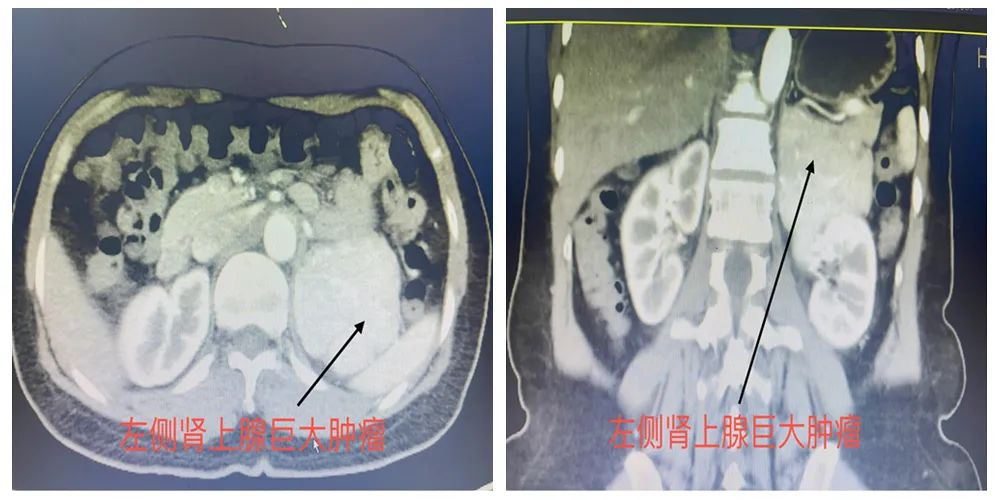

患者温女士,因反复胸闷心悸伴血压升高至我院就诊,完善彩超检查提示左肾上腺巨大占位。经我院泌尿外科会诊后转入泌尿外科进一步诊治。完善腹部增强CT提示:左侧肾上腺区占位:大小约78x68mm,增强扫描动脉期明显强化,考虑嗜铬细胞瘤(图1)。进一步完善腹部增强磁共振提示:左侧肾上腺区占位,T2WI及压脂序列呈高信号,内见条状血管影(图2)。检验结果提示,患者血、尿儿茶酚胺均呈明显异常升高。

▲图1:腹部增强CT所见